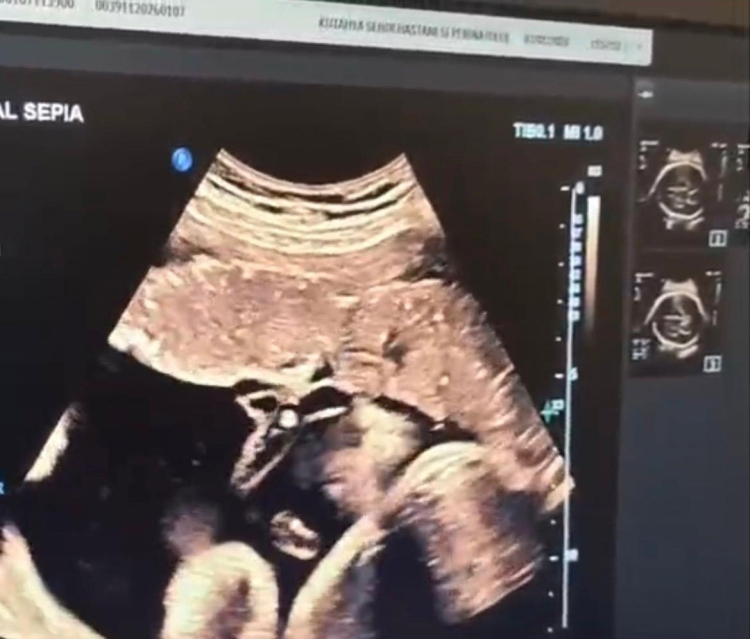

Halk arasında "anne karnında kan nakli" olarak bilinen intrauterin fetal kan transfüzyonu, bebekte ciddi kansızlık (anemi) tespit edilmesi halinde uygulanan hayati bir tedavi yöntemi olarak biliniyor. İşlem, ultrason eşliğinde anne karnından ince bir iğne yardımıyla bebeğin göbek kordonuna girilerek gerçekleştiriliyor. Önce bebeğin kan değerleri ölçülüyor, ardından eksik olan miktar kontrollü şekilde naklediliyor. Lokal anestezi altında ve steril şartlarda yapılan müdahale yaklaşık 30-45 dakika sürüyor.